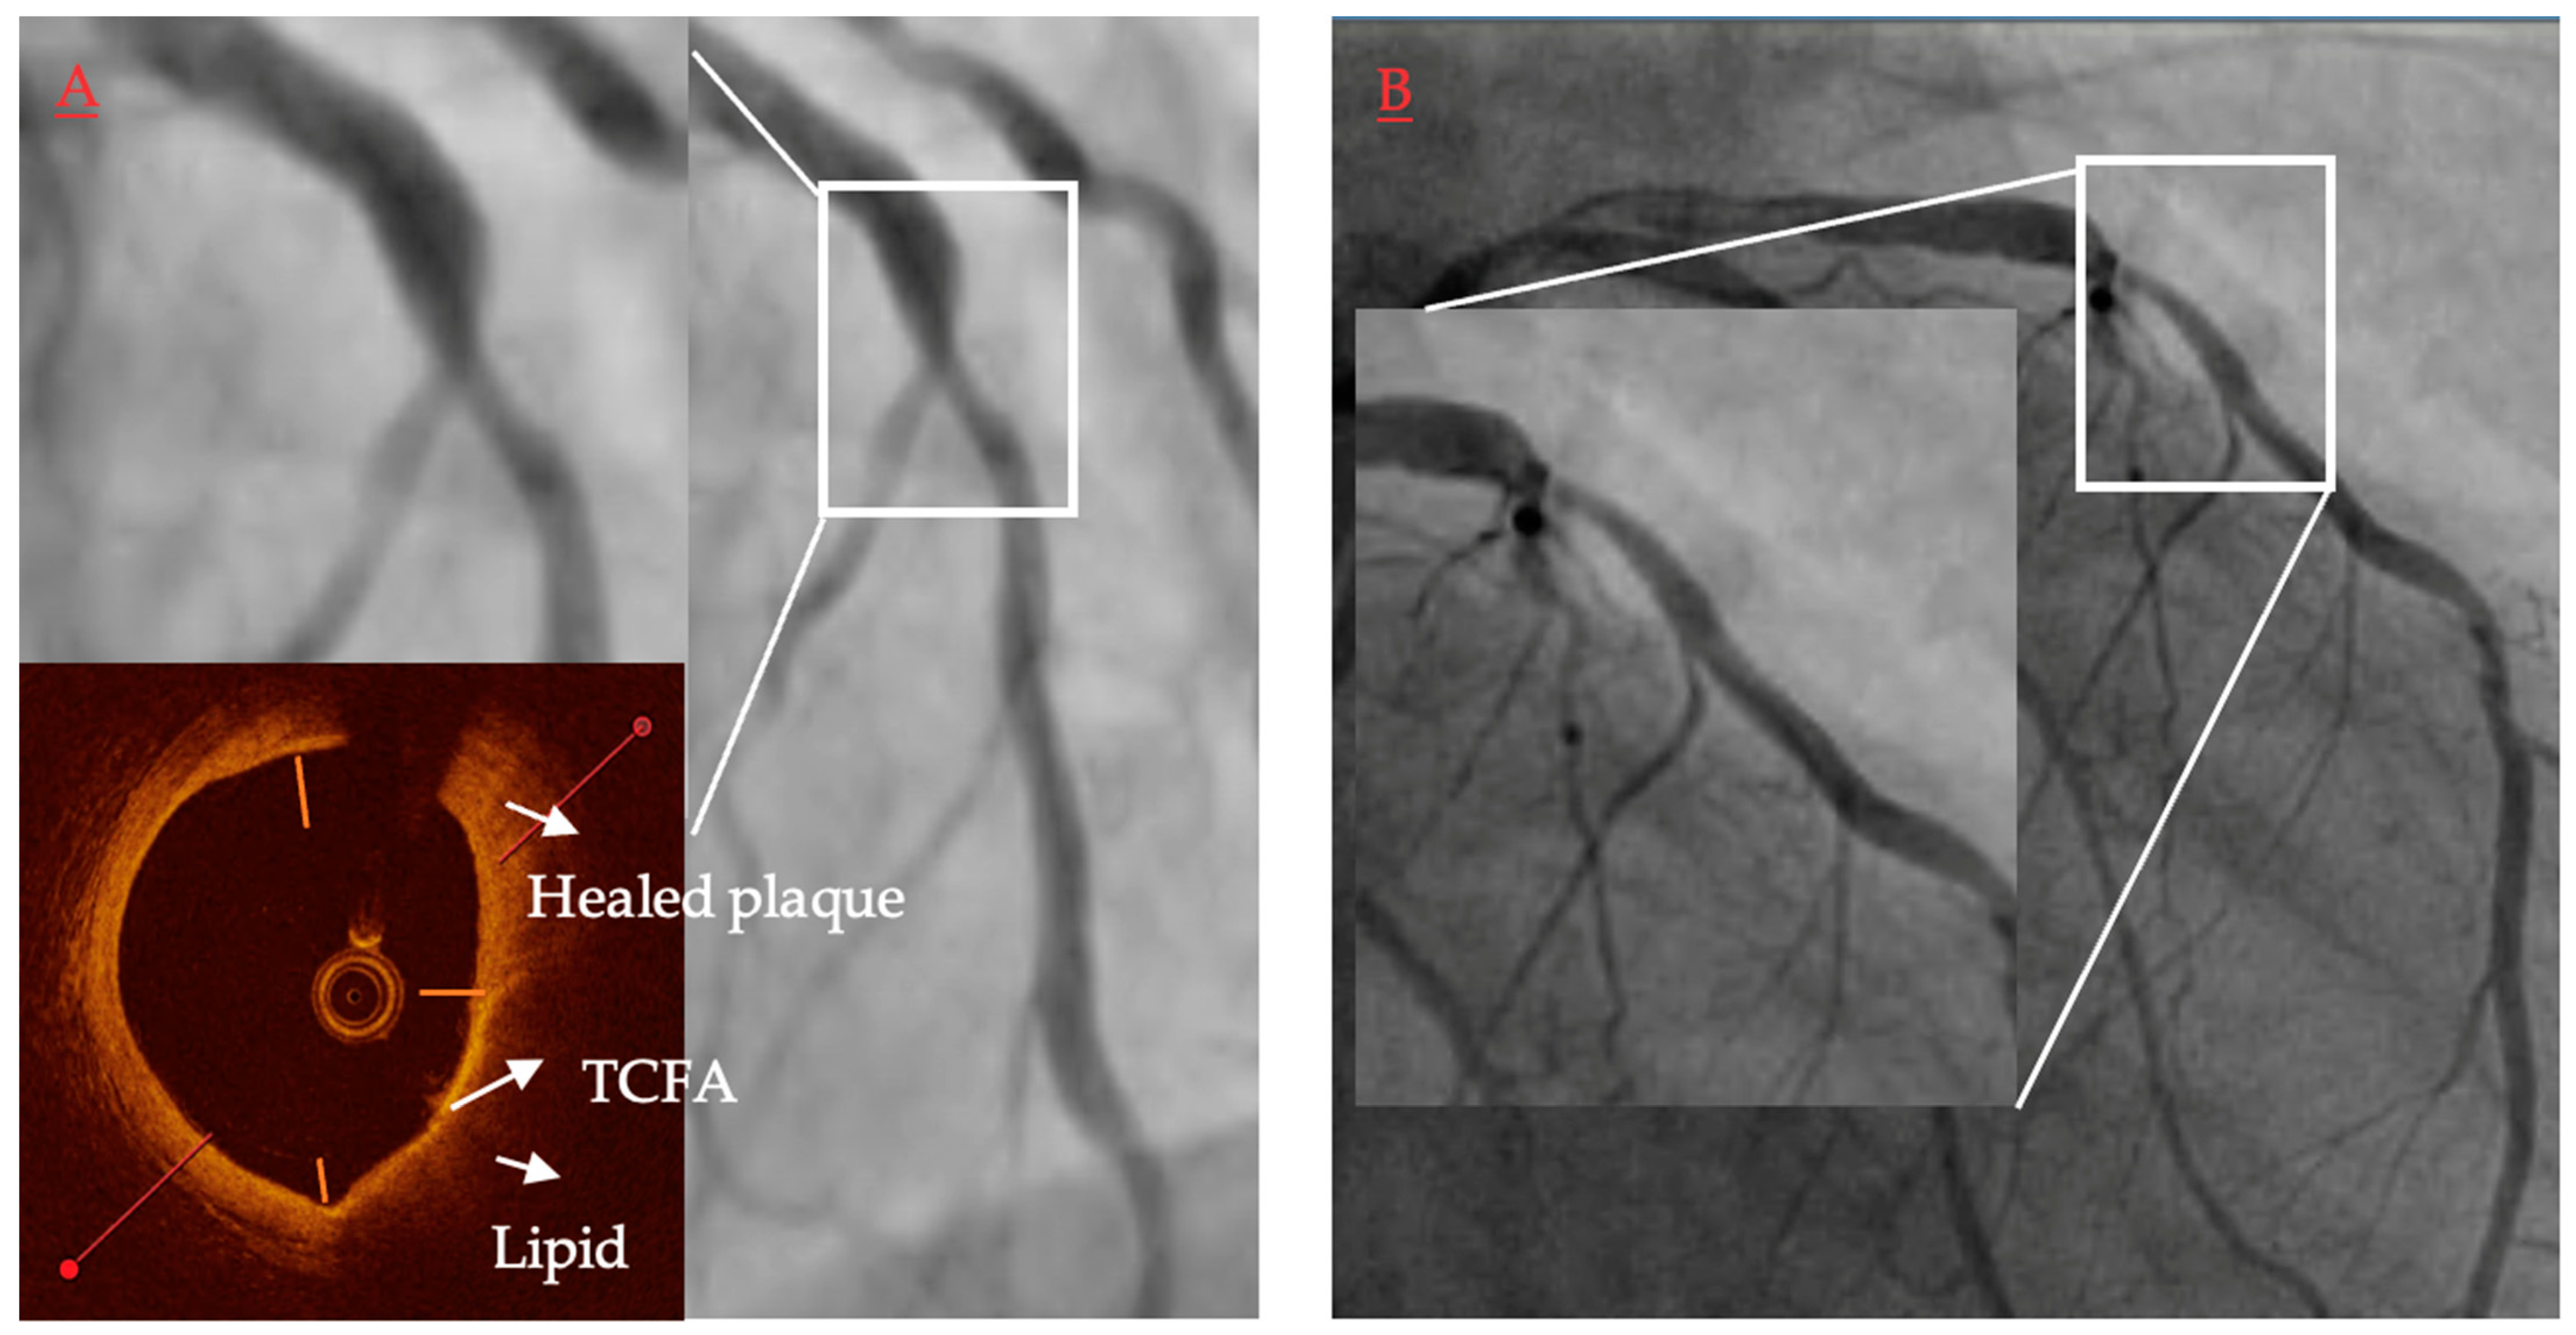

The initial studies presented the identification of long lipid and severely vessel narrowing lesions on OCT-identified patients at increased risk of MACE [61]. Recently, a published study, a COMBINE OCT-FFR trial, presented that the identification of TCFA in diabetic patients increased almost five times the risk of MACE at 18-months follow-up despite the absence of ischemia (Figure 5) [38]. This was the first trial shifting the concept of patients’ risk stratification from ischemia to plaque morphology. Importantly, a new subanalysis shows that not any lipidic plaque but only TCFA is related to future MACE, while ThCFA has very benign outcomes comparable to non-lipidic plaques. Comparable results were presented by Kubo et al. in a prospective study in which only lipid plaques were the cause of ACS during 6 years follow-up [62]. What is more important, ACS arose more frequently from lipid plaques with TCFA as compared to those with ThCFA (19% vs. 2%; HR 10.41 (95% CI: 6.48–16.73). Moreover, lipid-rich plaques (defined as lipid arc > 180 degrees) were also independent predictors of ACS. When combing both lipid-rich plaque and TCFA, those two features of plaque vulnerability were present in one third of all plaques, which caused ACS during the follow-up period. Intrudingly, macrophages were not predictors of future ACS events. On the contrary, in a CLIMA study, not only lipid-rich plaque and TCFA were predictors of major coronary events but also macrophages were associated with increased cardiac death or target vessel myocardial infarction. Discrepancy in those studies in regard to macrophages may be explained by subjectivity in the detection of macrophages and different criteria for cardiac endpoints. Regardless, it should be emphasized that macrophages are correlated with inflammation, which was found to be strongly associated with plaque vulnerability both in pathological and in vivo studies.

Figure 5.

Representative case of vulnerable plaque progression. (A) Thin-cap fibroatheroma (TCFA) located in a short lesion in left anterior descending, diameter stenosis 62%, FFR baseline 0.86. Presence of a TCFA 3–6 o’clock adjacent to a healed plaque 12–3 o’clock. (B) Same lesion 13.5 months later when patient presented with non-ST-elevation myocardial infarction and underwent revascularization.

While TCFA remains the cornerstone feature of vulnerable plaque studies, other plaque morphological characteristics, such as healed plaque, have recently also evolved as being at risk for future adverse events [61,69]. Recent insights from the COMBINE trial show that TCFA lesions that progressed to MACE were frequently located adjacent to healed plaque within the same lesion. Treatment modalities for this type of plaque remain to date unknown.